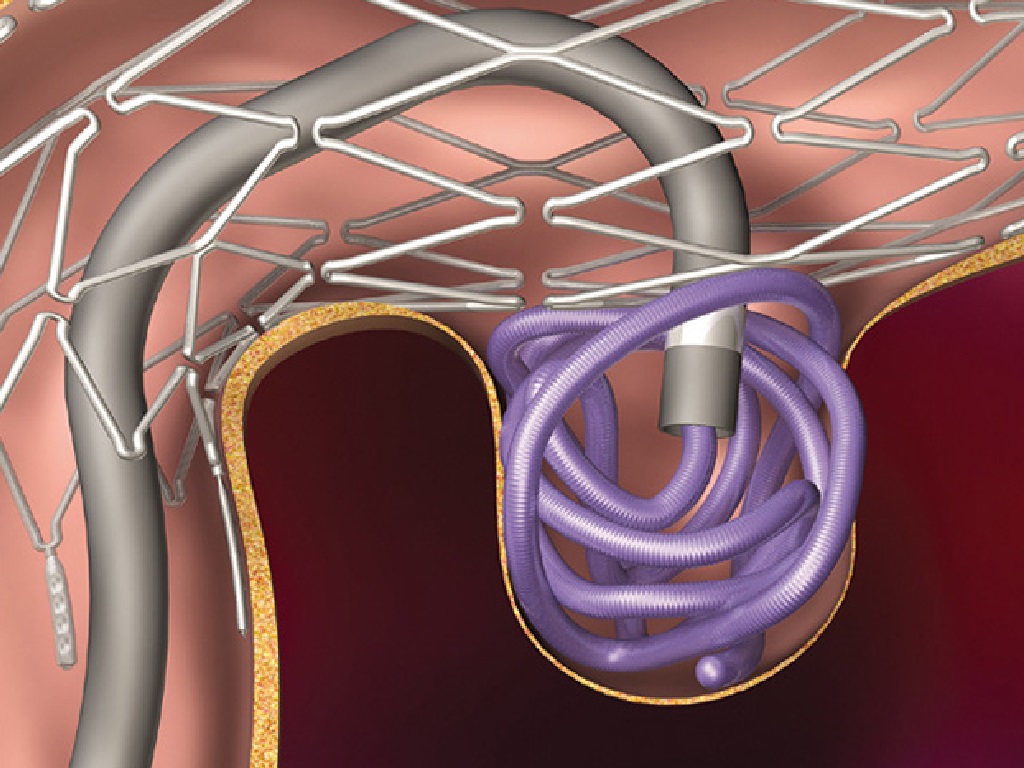

Снимки и иллюстрации микроаневризм сосудов головного мозга